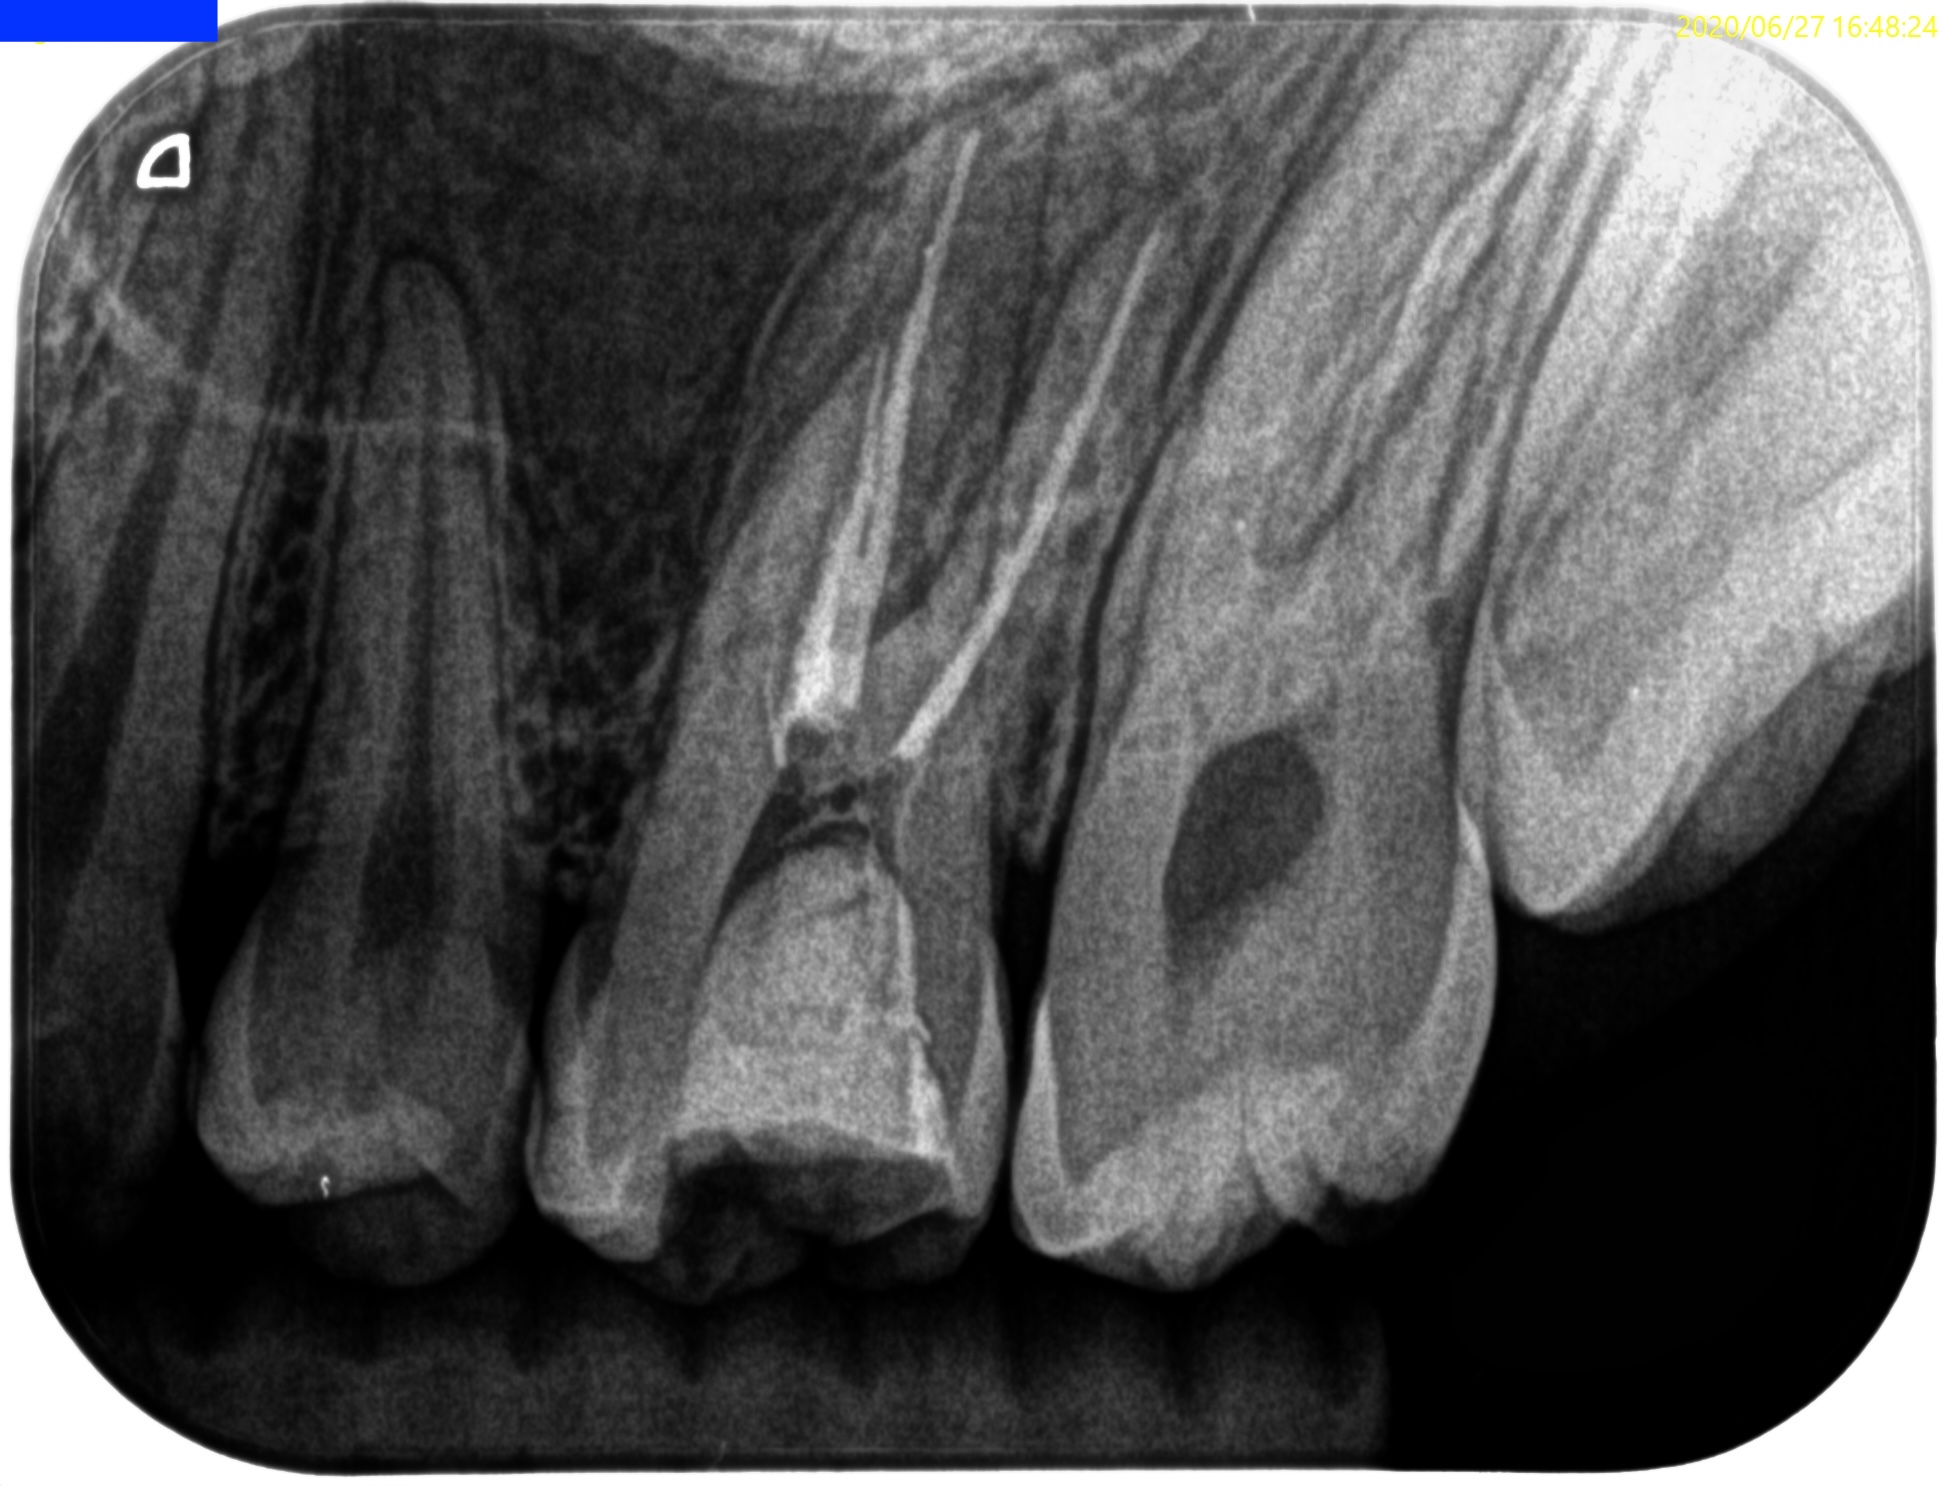

Pre-op Endo test(2020.6.27)

この時代は当歯科医院にCBCTがない時代で、非外科的な治療であるので撮影を外部へ依頼していない。

Pulp Dx: Previously treated

Periapical Dx: Symptomatic apical periodontitis

Recommended Tx: Re-RCT